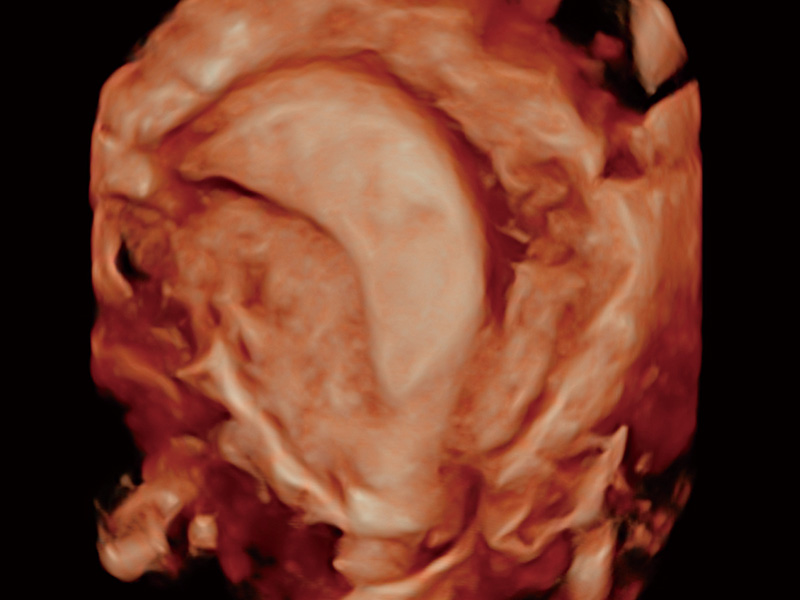

腔内容积探头

腔内三维成像技术获得显著提升,超大扇角在满足日常基础扫查的同时,支持卵泡自动测量及多种三维渲染模式,为您提供更多的诊断信息,尤其是在子宫畸形的诊断,内膜及肿瘤占位观测中起到了重要的作用。